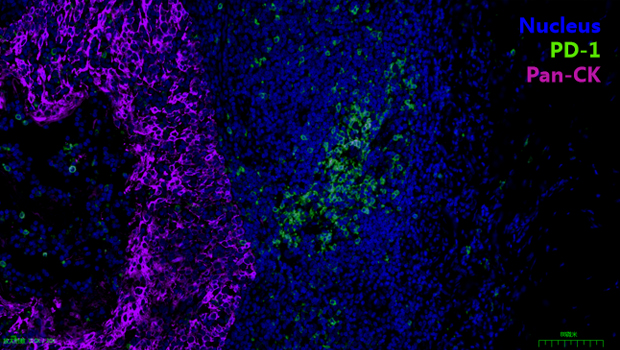

Nucleus, PD-1,Pan-CK